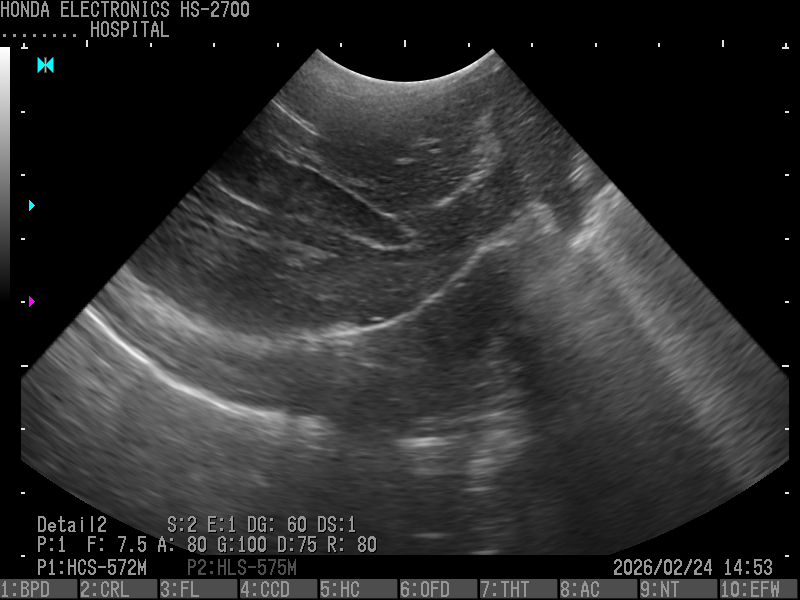

4.腎臓(パピヨン・10歳)

プローブ:HCS-572M

H-res:Detail2